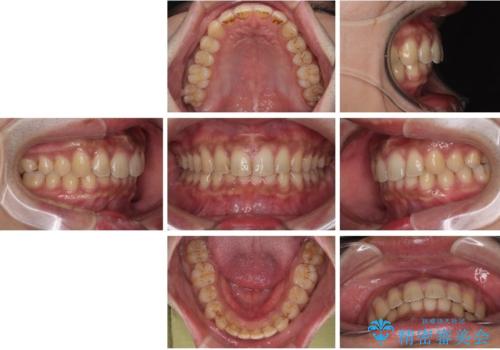

目立たない矯正で正中離開と下の前歯のデコボコを改善|インビザラインによる治療症例

- 上の前歯の正中離開(すきっ歯)と、下顎前歯部の叢生(デコボコ)を主訴に来院された患者様の症例です。

「目立ちにくい装置で治療したい」とのご希望があり、透明のマウスピース矯正であるインビザラインを用いて矯正治療を行いました。